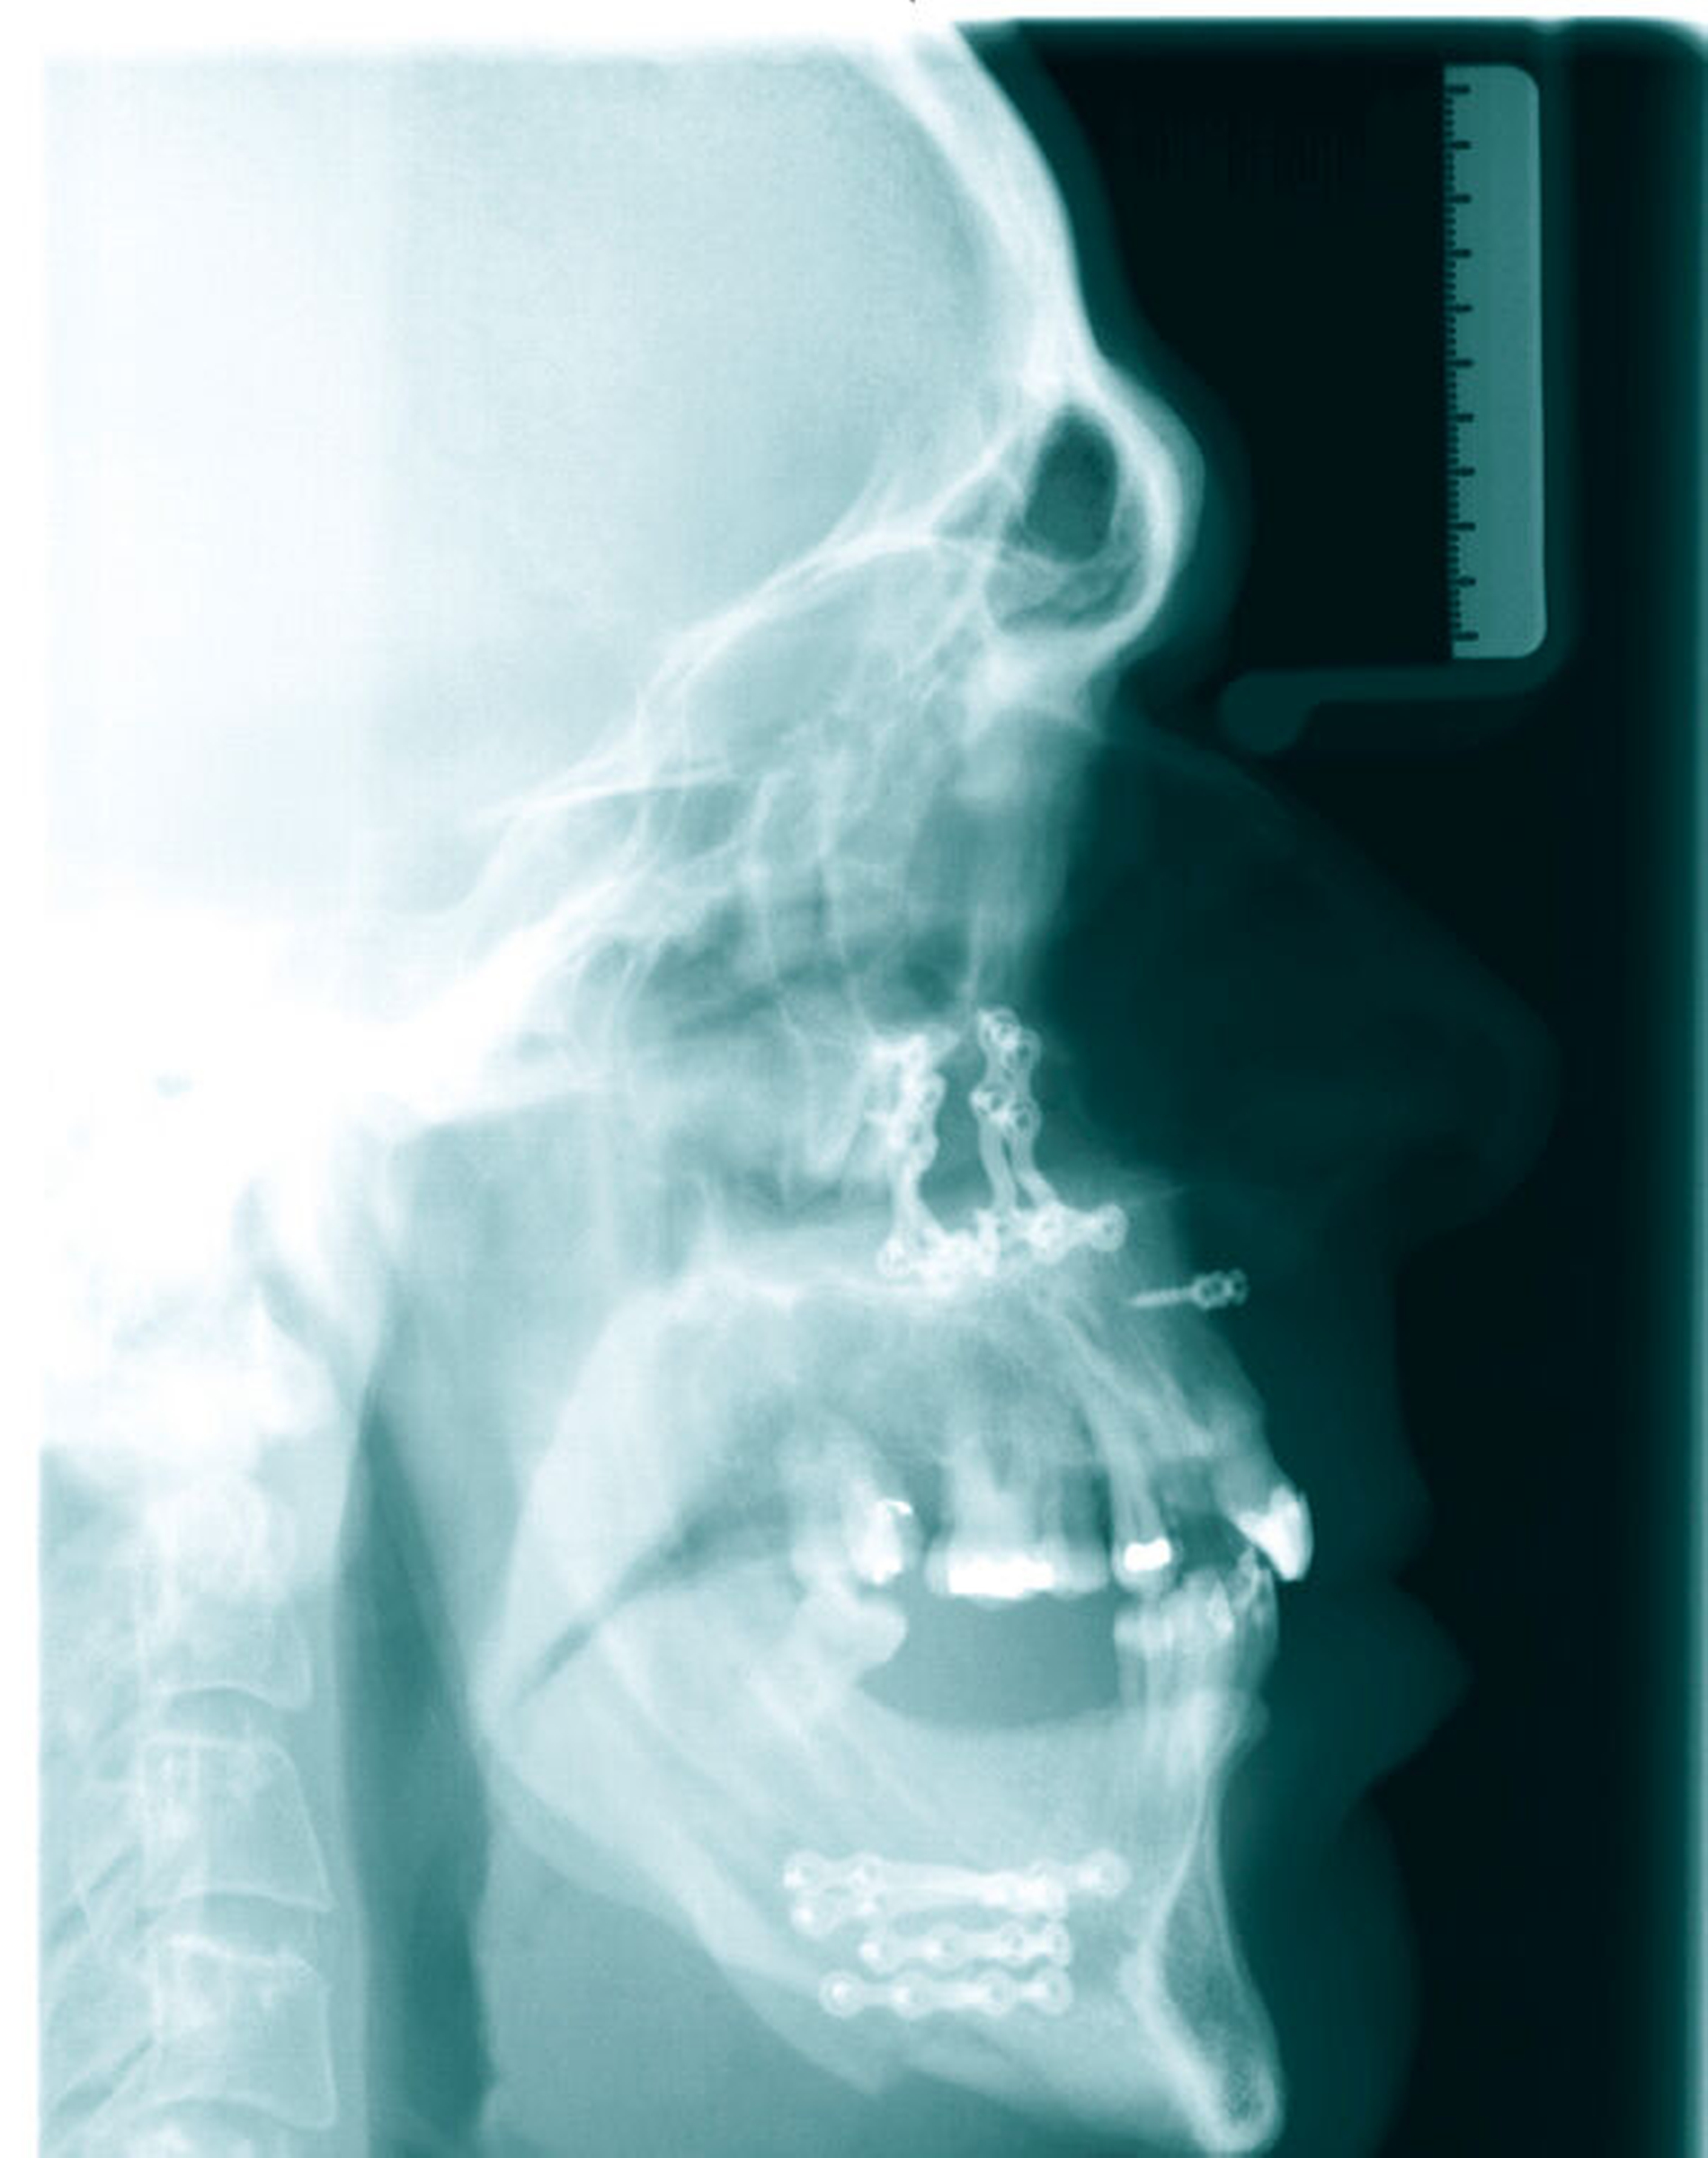

Die unverhältnismäßig große Zunge zeigte dentale Impressionen. Nach Festlegung des Zielbisses in Abstimmung mit den Kollegen der Prothetik erfolgte eine bimaxilläre Umstellungsosteotomie mit Vorverlagerung des Oberkiefers um 8 mm nach LeFort-I-Osteotomie und Rückverlagerung des Unterkiefers nach sagittaler retromolarer Osteotomie (Abbildungen 6 und 8). Im gleichen Zug wurde eine Zungenreduktionsplastik nach Rheinwald [Egyedi et al., 1964] durchgeführt.

Aufgrund der postoperativen schwellungsbedingten Atemwegseinengung wurde der Patient in dieser Zeit intensivmedizinisch betreut und prolongiert nach fünf Tagen extubiert. Er wurde letztlich am zwölften postoperativen Tag mit sicher gefundener Zielokklusion und deutlich harmonisiertem Gesichtsprofil locker verschnürt über einen prothetischen Interims-Zahnersatz aus der stationären Behandlung entlassen.